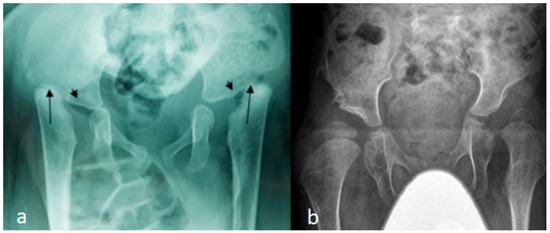

Figure 2.

(a,b): AP pelvis radiograph of a 7-month-old girl with Larsen syndrome showing bilateral hip dislocation associated with maldevelopment of severely dysplastic acetabulum and dysplastic capital femoral epiphysis (arrows) (a). AP pelvis radiograph of a 3-year-old boy with Larsen syndrome showing bilateral hip dislocations (severe acetabulo-femoral dysplasia) (b).